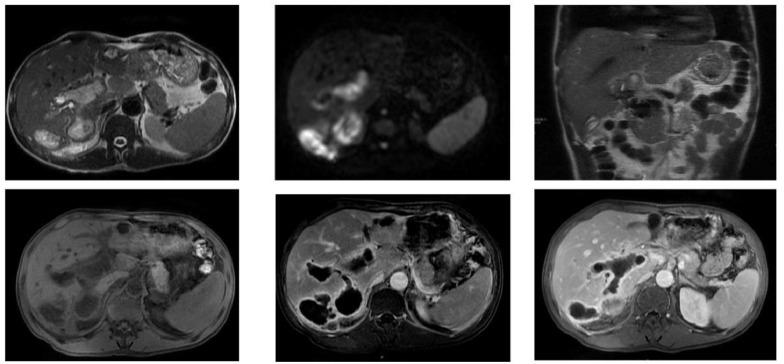

肝包虫囊肿破入门静脉:一种罕见的并发症。

Hydatid cyst of the liver rupturing into the portal vein: A rare complication.

Hydatid cyst of the liver is a zoonosis caused by parasite , which remains highly prevalent in Morocco. Current medical imaging modalities, particularly ultrasonography (US) and computed tomography (CT), facilitate rapid and accurate diagnosis, enable effective treatment possibilities and allow for easy follow-up. Complications are typically dominated by infection and rupture, especially in the bile ducts, peritoneal cavity, and chest. Dissemination and development within vascular structures, especially the portal vein, are much less common. This underscores the significance of our case, which illustrates this rare complication of hydatid cyst of the liver.

摘要

肝包虫囊肿是一种由寄生虫引起的人畜共患病,在摩洛哥仍然高度流行。当前的医学成像方式,尤其是超声检查(US)和计算机断层扫描(CT),有助于快速准确的诊断,提供有效的治疗可能性并便于随访。并发症通常以感染和破裂为主,尤其是在胆管、腹腔和胸部。在血管结构内,尤其是门静脉内的播散和发展则要少见得多。这凸显了我们病例的重要性,该病例说明了肝包虫囊肿这种罕见的并发症。